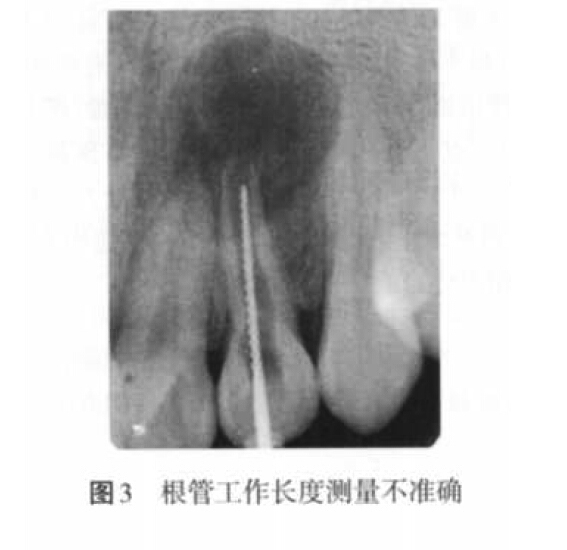

(2)超充原因:主要包括預(yù)備成形不良、根尖孔大而主牙膠尖過(guò)?。▓D4)、根管工作長(zhǎng)度測(cè)量不準(zhǔn)確、根充技術(shù)選擇不當(dāng)以及術(shù)者操作不當(dāng)?shù)仍颉?/p>